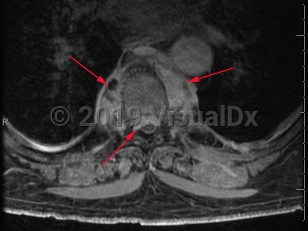

Paraspinal abscess is a collection of pus located around the spinal cord. This is usually seen as a complication of vertebral osteomyelitis and discitis (diskitis) but may be related to hematogenous seeding during bloodstream infection. Epidural catheters and injections may lead to direct inoculation of the epidural space. Frequently, the location of the abscess is in the epidural space.

Patients may have acute (develops over hours) or subacute (develops over weeks to months) back pain. Fever may or may not be present. As the abscess forms, patients typically have focal and severe back pain. As the size of the abscess increases, it may impinge on the spinal cord, leading to signs of spinal cord compression, including motor weakness and sensory deficits. Untreated, the patient's neurologic symptoms can worsen to the point of irreversible paralysis.